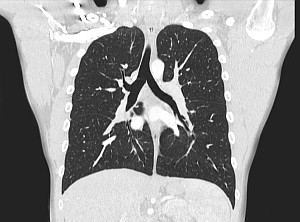

Легкие и Средостение

Органы грудной клетки